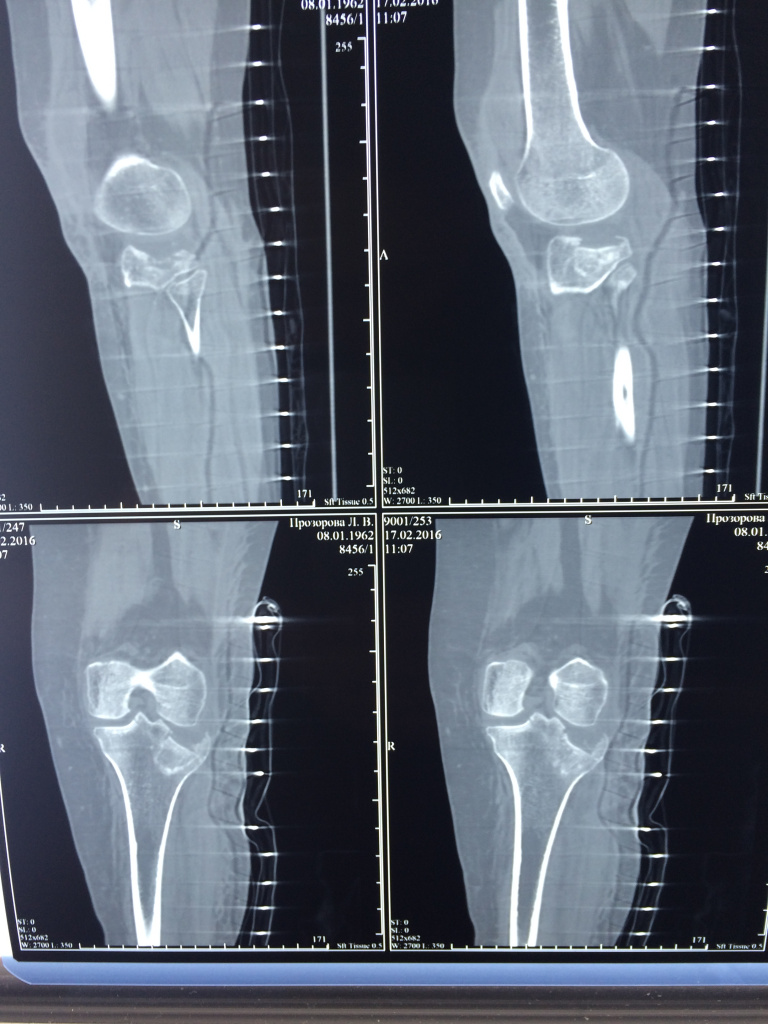

Использование материала Остеоматрикс при импрессионном оскольчатом переломе наружного мыщелка большеберцовой кости по типу Schatzker II

Использование материала Остеоматрикс при импрессионном оскольчатом переломе наружного мыщелка большеберцовой кости по типу Schatzker II.

Операция - открытая репозиция, остеосинтез большеберцовой кости опорной пластиной с костной ксенопластикой маетриалом "Остеоматрикс". На контрольных снимках в три и шесть месяцев имеется консолидация перелома, миграции фиксатора нет, имеется остеоинтеграция ксенопластического материала. Функция коленного сустава полная.